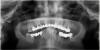

SergeyAL Опубликовано 15 мая, 2013 Поделиться Опубликовано 15 мая, 2013 а височнонижнечелюстной сустав у Вас не болит, не щелкает при широком открывании? Есть ли на коронках сколы керамического покрытия?Я это спрашиваю, потому что судя по данной ортопантомограмме (не самого лучшего качества) у Вас выраженное снижение межальвеолярной высоты (видны изменения в области суставов), и протезировать Вас в таком прикусе может быть опасно и для суставов, и для керамических коронок, и для имплантатов. Поэтому, скорее всего необходимо сначала определять правильную высоту прикуса, ходить с различными каппами и только после этого думать о плане протезирования. Если есть какие-то остро беспокоящие зубы с ними можно решить вопрос в первую очередь, но потом по протоколу.... Ссылка на комментарий